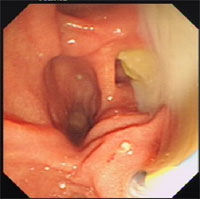

急性化膿性膽管炎腸鏡圖片病因

3.腫瘤腫瘤是引起APC的重要原因,主要是膽道及壺腹周圍的腫瘤,以惡性腫瘤居多。腫瘤的生長引起膽道梗阻,膽汁排泄不暢,淤積的膽汁繼發細菌感染而引起APC。值得注意的是,在膽道梗阻原因不清時,為了明確診斷,施行膽道侵入性檢查,如ERCP檢查時極容易將細菌帶入膽道,患者在檢查結束後即出現腹痛、發熱等一系列急性膽管炎的症狀。APC的出現給腫瘤的治療帶來極大困難,增加了手術的危險性,甚至使病人錯過根治性切除的時機。因此,在梗阻性黃疸的患者,疑為膽道或壺腹周圍的腫瘤時,ERCP等膽道侵入性檢查應特別慎重,如必須進行,可同時放入鼻膽管引流,以預防APC的發生。對於十二指腸乳頭部腫瘤,可採用十二指腸鏡下觀察及切取活體組織做病理檢查,不做逆行胰膽管造影。

(2)內鏡治療:對於膽管炎病因不明者;非手術治療24~36h無效或病情加重者;年齡較大,伴發病較多或重,手術麻醉風險較大者;有多次膽道手術史者,均可行急診內鏡膽道減壓引流,包括十二指腸乳頭括約肌切開術並取石,或經鼻胃管或內鏡導管(鼻膽管)引流膽汁。有研究顯示內鏡治療確實有效,並可降低病死率。急性膽管炎行急診內鏡EST和取石的指征為:

急性化膿性膽管炎病理圖片預防:急性化膿性膽管炎是肝膽管結石、膽道蛔蟲症的嚴重併發症,故該病的一級預防主要是針對肝膽管結石及膽道蛔蟲的防治。①防治肝膽管結石,肝膽管結石的預防關鍵在於預防及消除致病因素。而已確診為肝膽管結石的病人,則應高度警惕本病的發生,尤其在並發膽道感染時應更積極地防治。早期即套用大劑量敏感抗生素抗感染,注意水、電解質及酸鹼平衡,加強全身支持治療控制膽道感染。在全身情況允許的情況下儘早手術,去除結石,通暢引流,從而達到預防AOST的發生。②防治膽道蛔蟲症。蛔蟲進入膽道後造成膽道不同程度的梗阻,使膽道壓力增高,當並發細菌感染時,可誘發AOST。另外,膽道蛔蟲症也是肝膽管結石形成的重要因素。因此,防治膽道蛔蟲症是預防AOST的極其重要的方面。主要是注意飲水、飲食衛生,防治腸道蛔蟲病。一旦確診即行驅蛔治療,如已確診為膽道蛔蟲症,則應儘快治療。給予鎮痛、解痙、控制感染,促使蛔蟲自行從膽道退出。另外,可作十二指腸內鏡檢查,用圈套器將部分進入膽總管口的蛔蟲套住拉出體外。治療無效時方考慮手術治療。